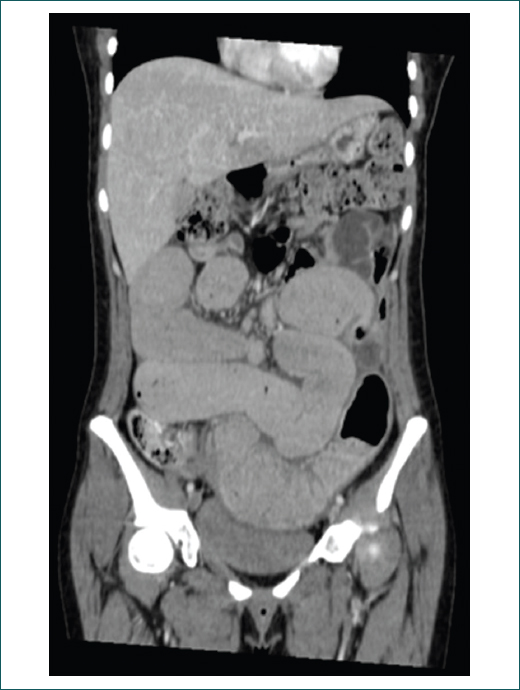

Como parte del protocolo diagnóstico se realiza una tomografía abdominal que reporta probable apendicitis complicada; valorada por el servicio de cirugía general, se descarta la presencia de patología apendicular. Por el antecedente de pérdida de peso cuantificada de 18 kg en 3 meses, ingresa al servicio de medicina interna para inicio de protocolo de estudio, en donde se evidencia en los estudios iniciales anemia normocítica normocrómica, así como trombocitosis. Se realiza radiografía de abdomen simple y en decúbito, que muestra una importante dilatación de asas intestinales a expensas del yeyuno y el íleon. La tomografía de abdomen en fase simple y contrastada muestra una imagen compatible con una zona de estenosis a nivel del íleon distal, a 7 cm de la válvula ileocecal, que de forma secundaria condiciona un proceso pseudooclusivo, además de compresión y desplazamiento de estructuras pélvicas (útero, vejiga y sigmoides) (Figs. 1 y 2).